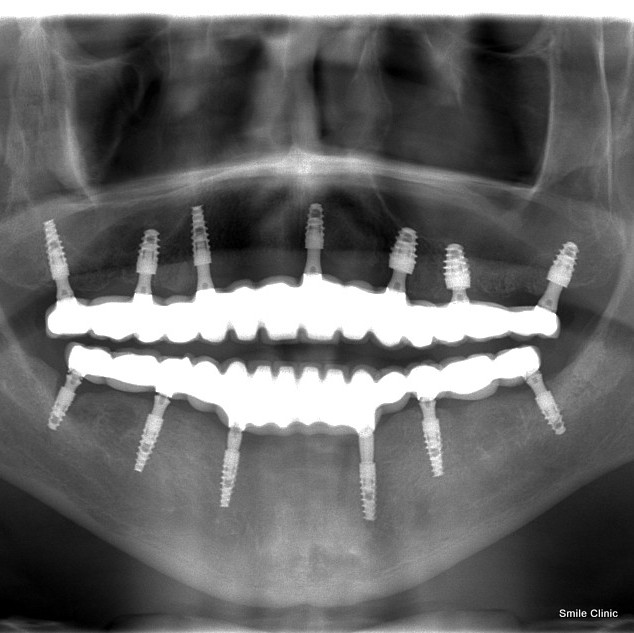

For this patient we placed 13 dental implants to support 14 porcelain crowns as bridgework on both the upper and lower jaw in 3 short visits over half a year.